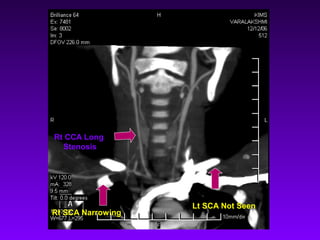

Rt CCA Long

Stenosis

Lt SCA Not Seen

Rt SCA Narrowing

Rt CCA Long Stenosis Lt SCA Not Seen Rt SCA Narrowing